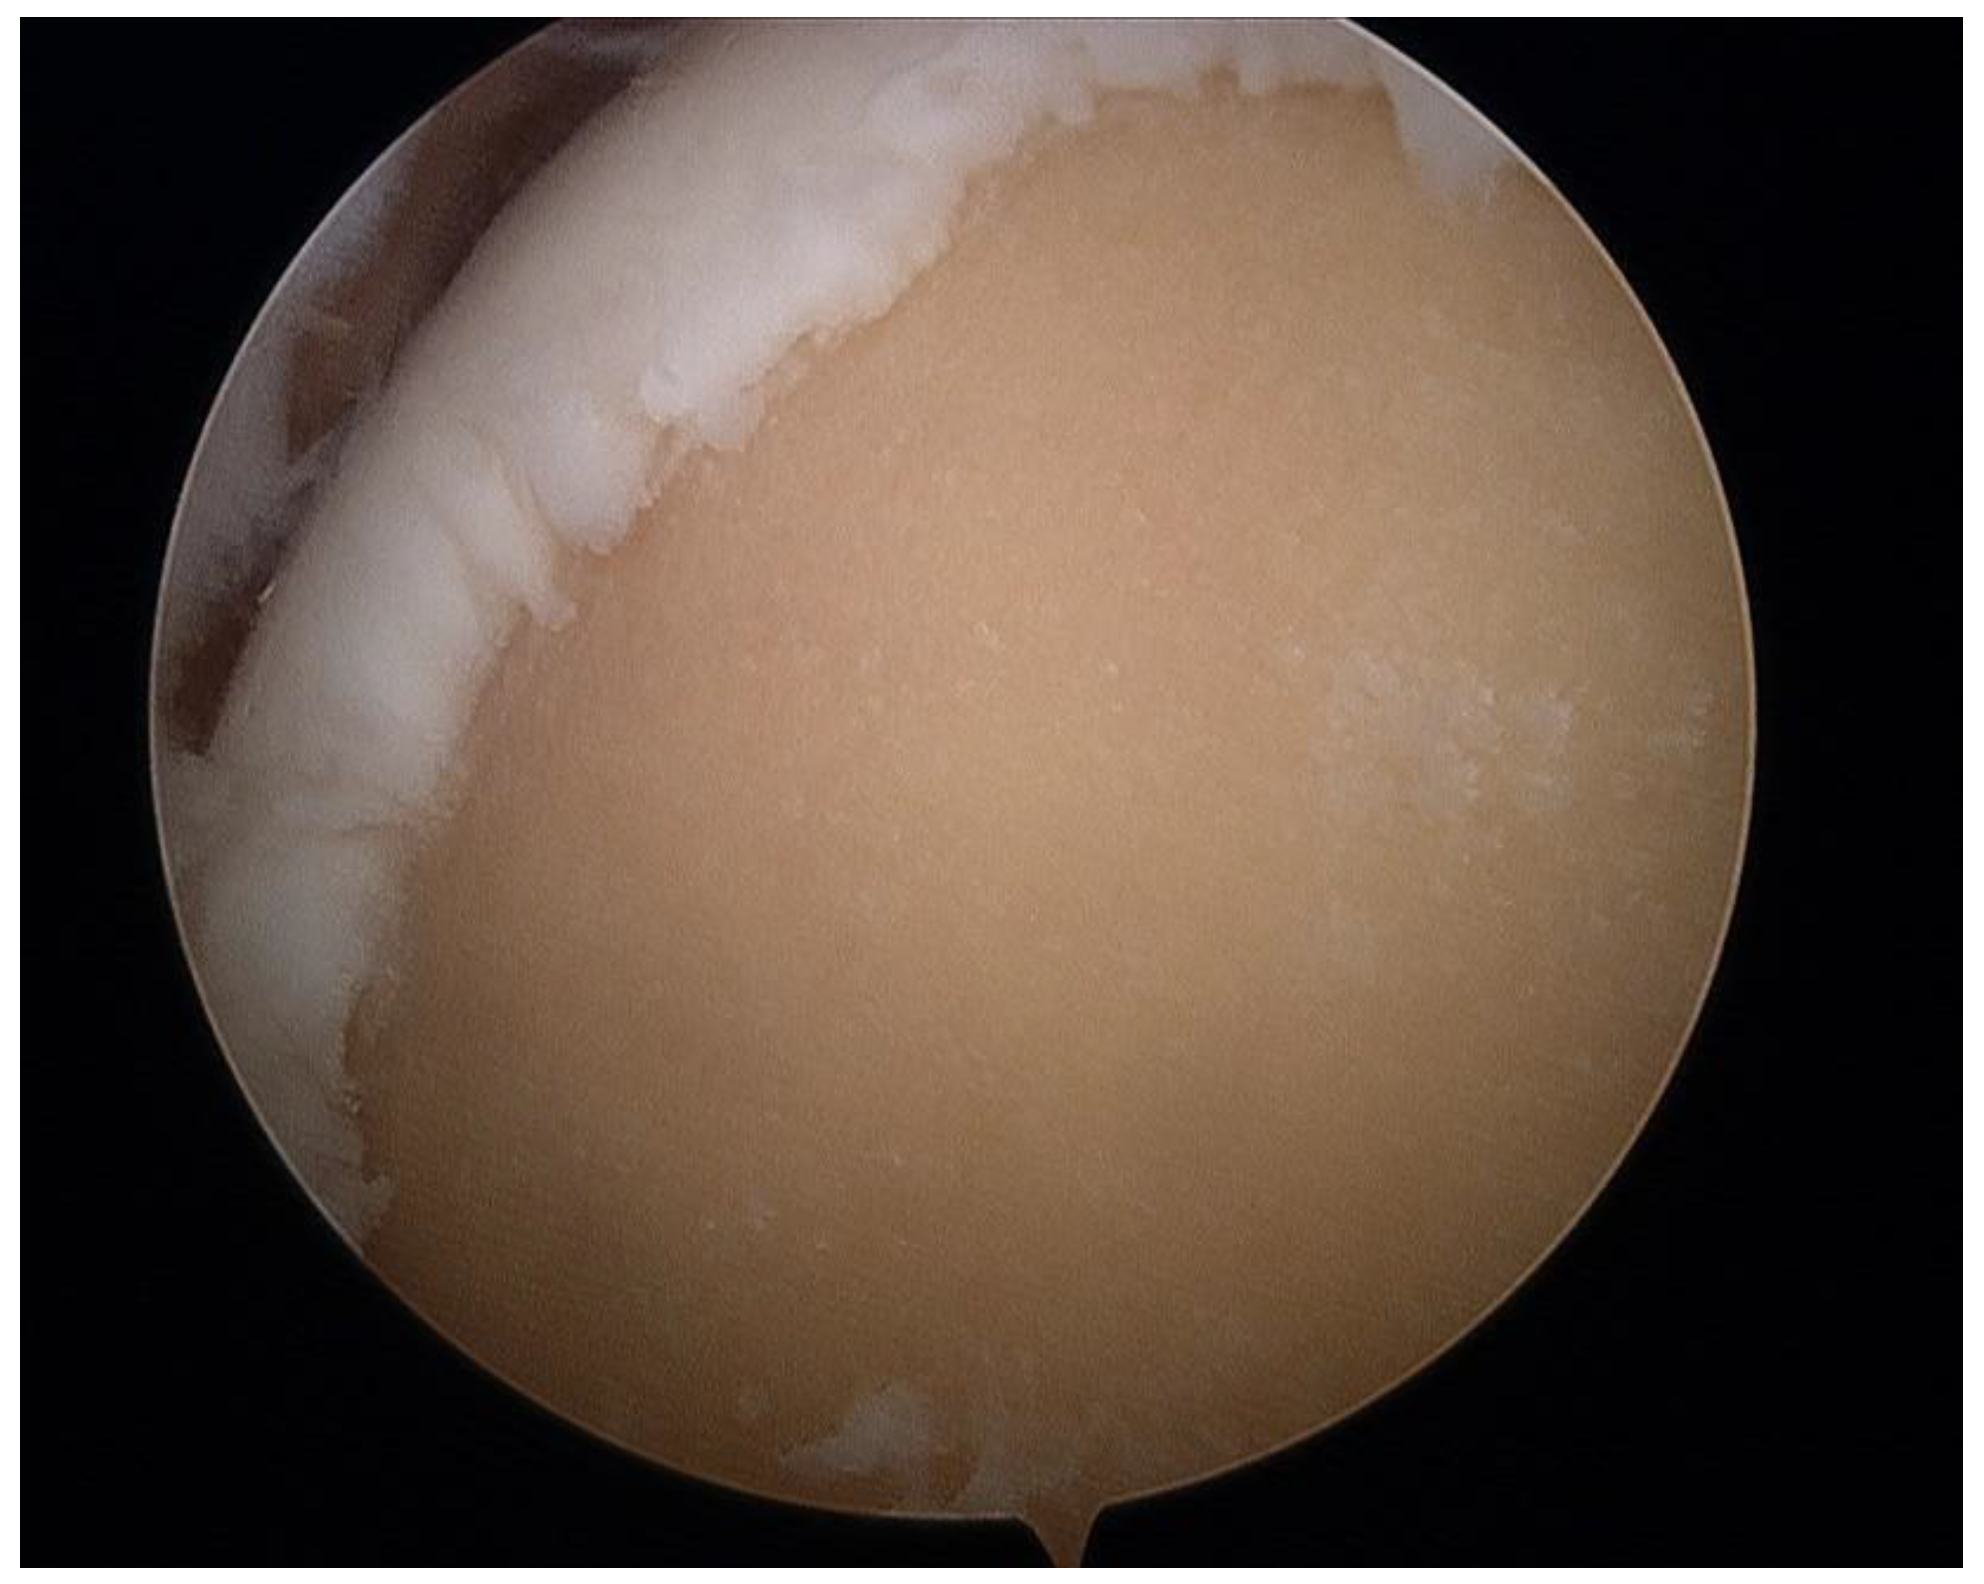

:1. Introduction

2.2. Surgical Procedure

3. Results